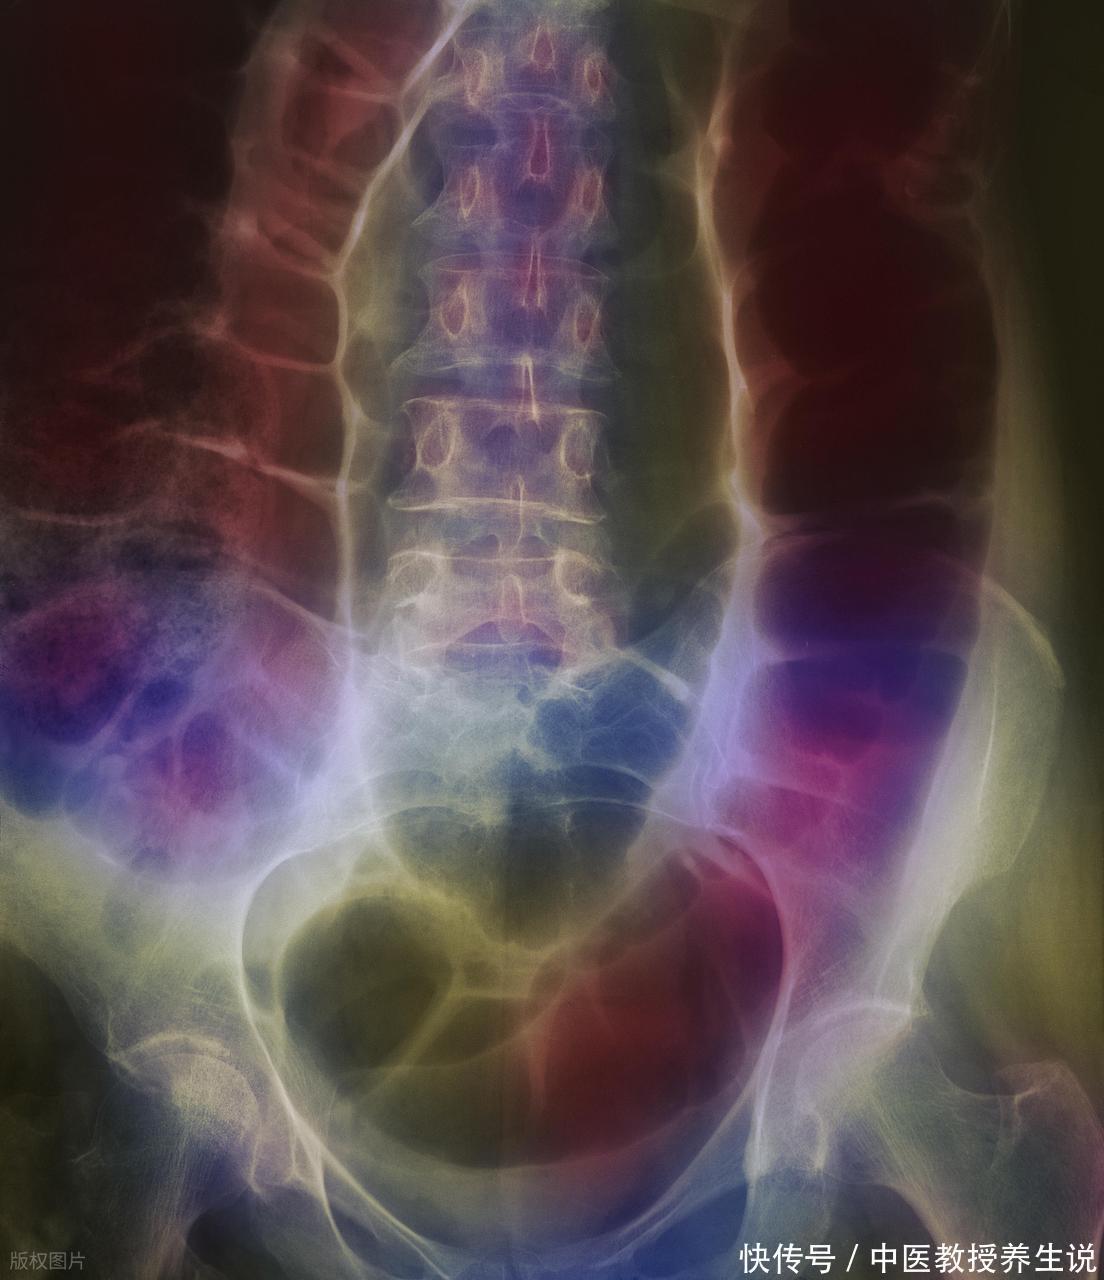

没完没了的腹泻交替着便秘,体重在一个月内部不经意间往下掉七八斤。别把这种折磨全扣在普通肠炎头上。右下腹那持续的隐痛,往往是一场更凶险的侵蚀性破坏的掩护。要是长期按普通胃痛规律去吃抗菌消炎药,炎症指标根本压不住,最终等来的可能是肠梗阻甚至肠穿孔。夜里痛得蜷缩在床,做便常规往往抓不到源头,潜伏在消化道深处的元凶,远比常见的肠道致病微生物狡猾。

肺部游离的致病菌顺着血液转移,或随着被吞咽的呼吸道分泌物进入消化道安营扎寨,便是肠结核。这种特异性感染如同白蚁啃噬木材般,持续破坏着平滑的肠壁组织。